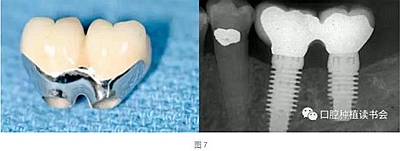

天然牙的預(yù)備通常限制刃狀邊緣的使用以避免最終修復(fù)體外形過(guò)凸。沒(méi)有具體的研究表明凹形邊緣完成線比其他的完成線形態(tài)更優(yōu)越,但易于預(yù)備的特點(diǎn)是選擇它們的理由,而且避免了修復(fù)體過(guò)大。修復(fù)學(xué)中存在幾種常見(jiàn)的刃狀邊緣預(yù)備的適應(yīng)證,因?yàn)樗鼈冎恍枰獦O小的切削量。適應(yīng)證包括:①種植體基臺(tái)(圖7);②磨牙和前磨牙的根分叉區(qū)域;③下頜切牙的鄰間隙區(qū)域;④下頜后牙的舌側(cè)面;⑤軸面特別凹(非常凸的軸向表面);⑥傾斜超過(guò)15°的基牙軸面。

種植體基臺(tái)使用刃狀邊緣的一個(gè)例外是當(dāng)種植體過(guò)于偏頰側(cè)或距離鄰牙過(guò)近,同時(shí)要制作瓷冠邊緣時(shí)。在種植體位置過(guò)于偏頰側(cè)的情況下,可以選擇肩臺(tái)或淺凹邊緣的冠邊緣設(shè)計(jì),為修復(fù)創(chuàng)造足夠的空間并避免修復(fù)體外形過(guò)凸(圖8)。粘接固位基臺(tái)邊緣的位置要位于游離齦緣1±0.5 mm的范圍內(nèi),過(guò)深的邊緣容易導(dǎo)致粘接劑殘留,造成種植體周圍炎(圖9)。